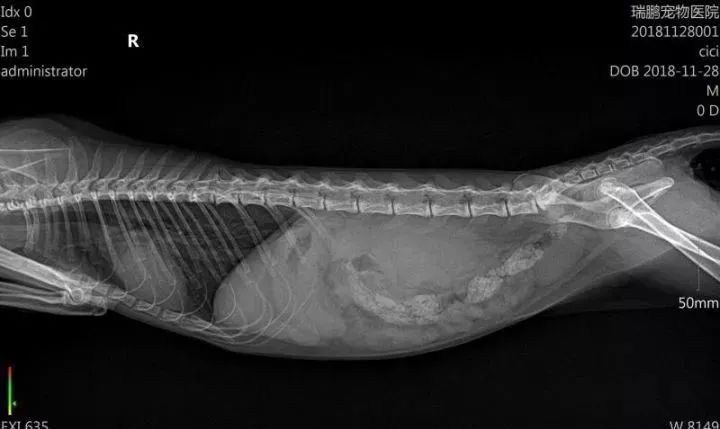

在11月25号我带它去宠物医院,拍片—抽血。

于是我转战到另外一个宠物医院,医生接手了,于是又一次化验-做B超及其他检验,隔天才有结果,等到第二天,医生告诉我是“肾脏大”